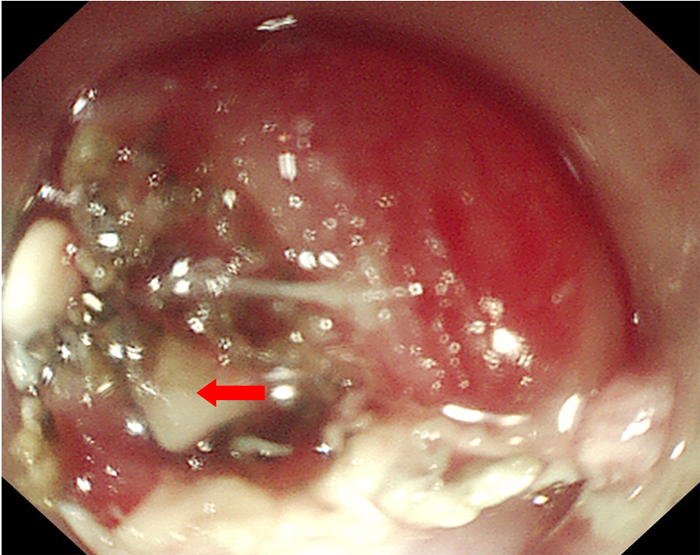

近日,我院李曙晖主任医师在内镜中心护理、麻醉团队密切配合下,通过内镜下食管黏膜剥离术,成功为一辗转3家医院食管异物1周的患者取出3cm鱼刺。12月18日,患者陈某在进食鱼后出现咽部异物感,伴有吞咽痛,19日在当地医院行胸部CT示食管异物待排,胃镜示创伤性食管炎,食管内未见明显异物。3天后,患者咽部异物感等症状无缓解,于我市另一医院复查胸部CT示食管上段异物,再次行胃镜检查示食管黏膜损伤,未见异物。胸外科会诊认为如果外科手术,创伤大,建议患者首选内镜下微创手术。因此,患者慕名前来我院就诊,收住消化内科一病区。为了解鱼刺与周围的关系及是否刺入血管,患者入院后给予完善胸部强化CT,示胸上段管腔内高密度影,考虑食管异物。李曙晖主任医师结合患者病史、2次胃镜结果及胸部CT等,分析认为鱼刺已深深扎入食管壁内,可行食管黏膜剥离术暴露出异物后再行取出。12月28日,李曙晖主任医师在麻醉和护理团队的配合下行胃镜检查,内镜下距门齿18cm可见食管黏膜充血水肿,未见异物,遂用黏膜切开刀切开周围黏膜及肌层,暴露出异物顶端,再用鳄口钳钳住鱼刺顶端,顺利取出一枚长3cm多的鱼刺,看到大部分鱼刺扎入食管壁。术后对症治疗后,患者现已痊愈出院。李曙晖主任医师提醒,食管异物可发生在任何年龄段,而且异物种类多样,以鱼刺、肉骨最为常见。一旦发生异物卡喉或消化道异物,用醋、团饭、菜叶等吞咽均不可取,这些做法最大的可能是将鱼刺越压越紧、扎得更深,如果是比较大的刺还有可能刺破食管或血管,危害更大。正确的处理是立即停止进食,及时就医,不能抱有侥幸心理。